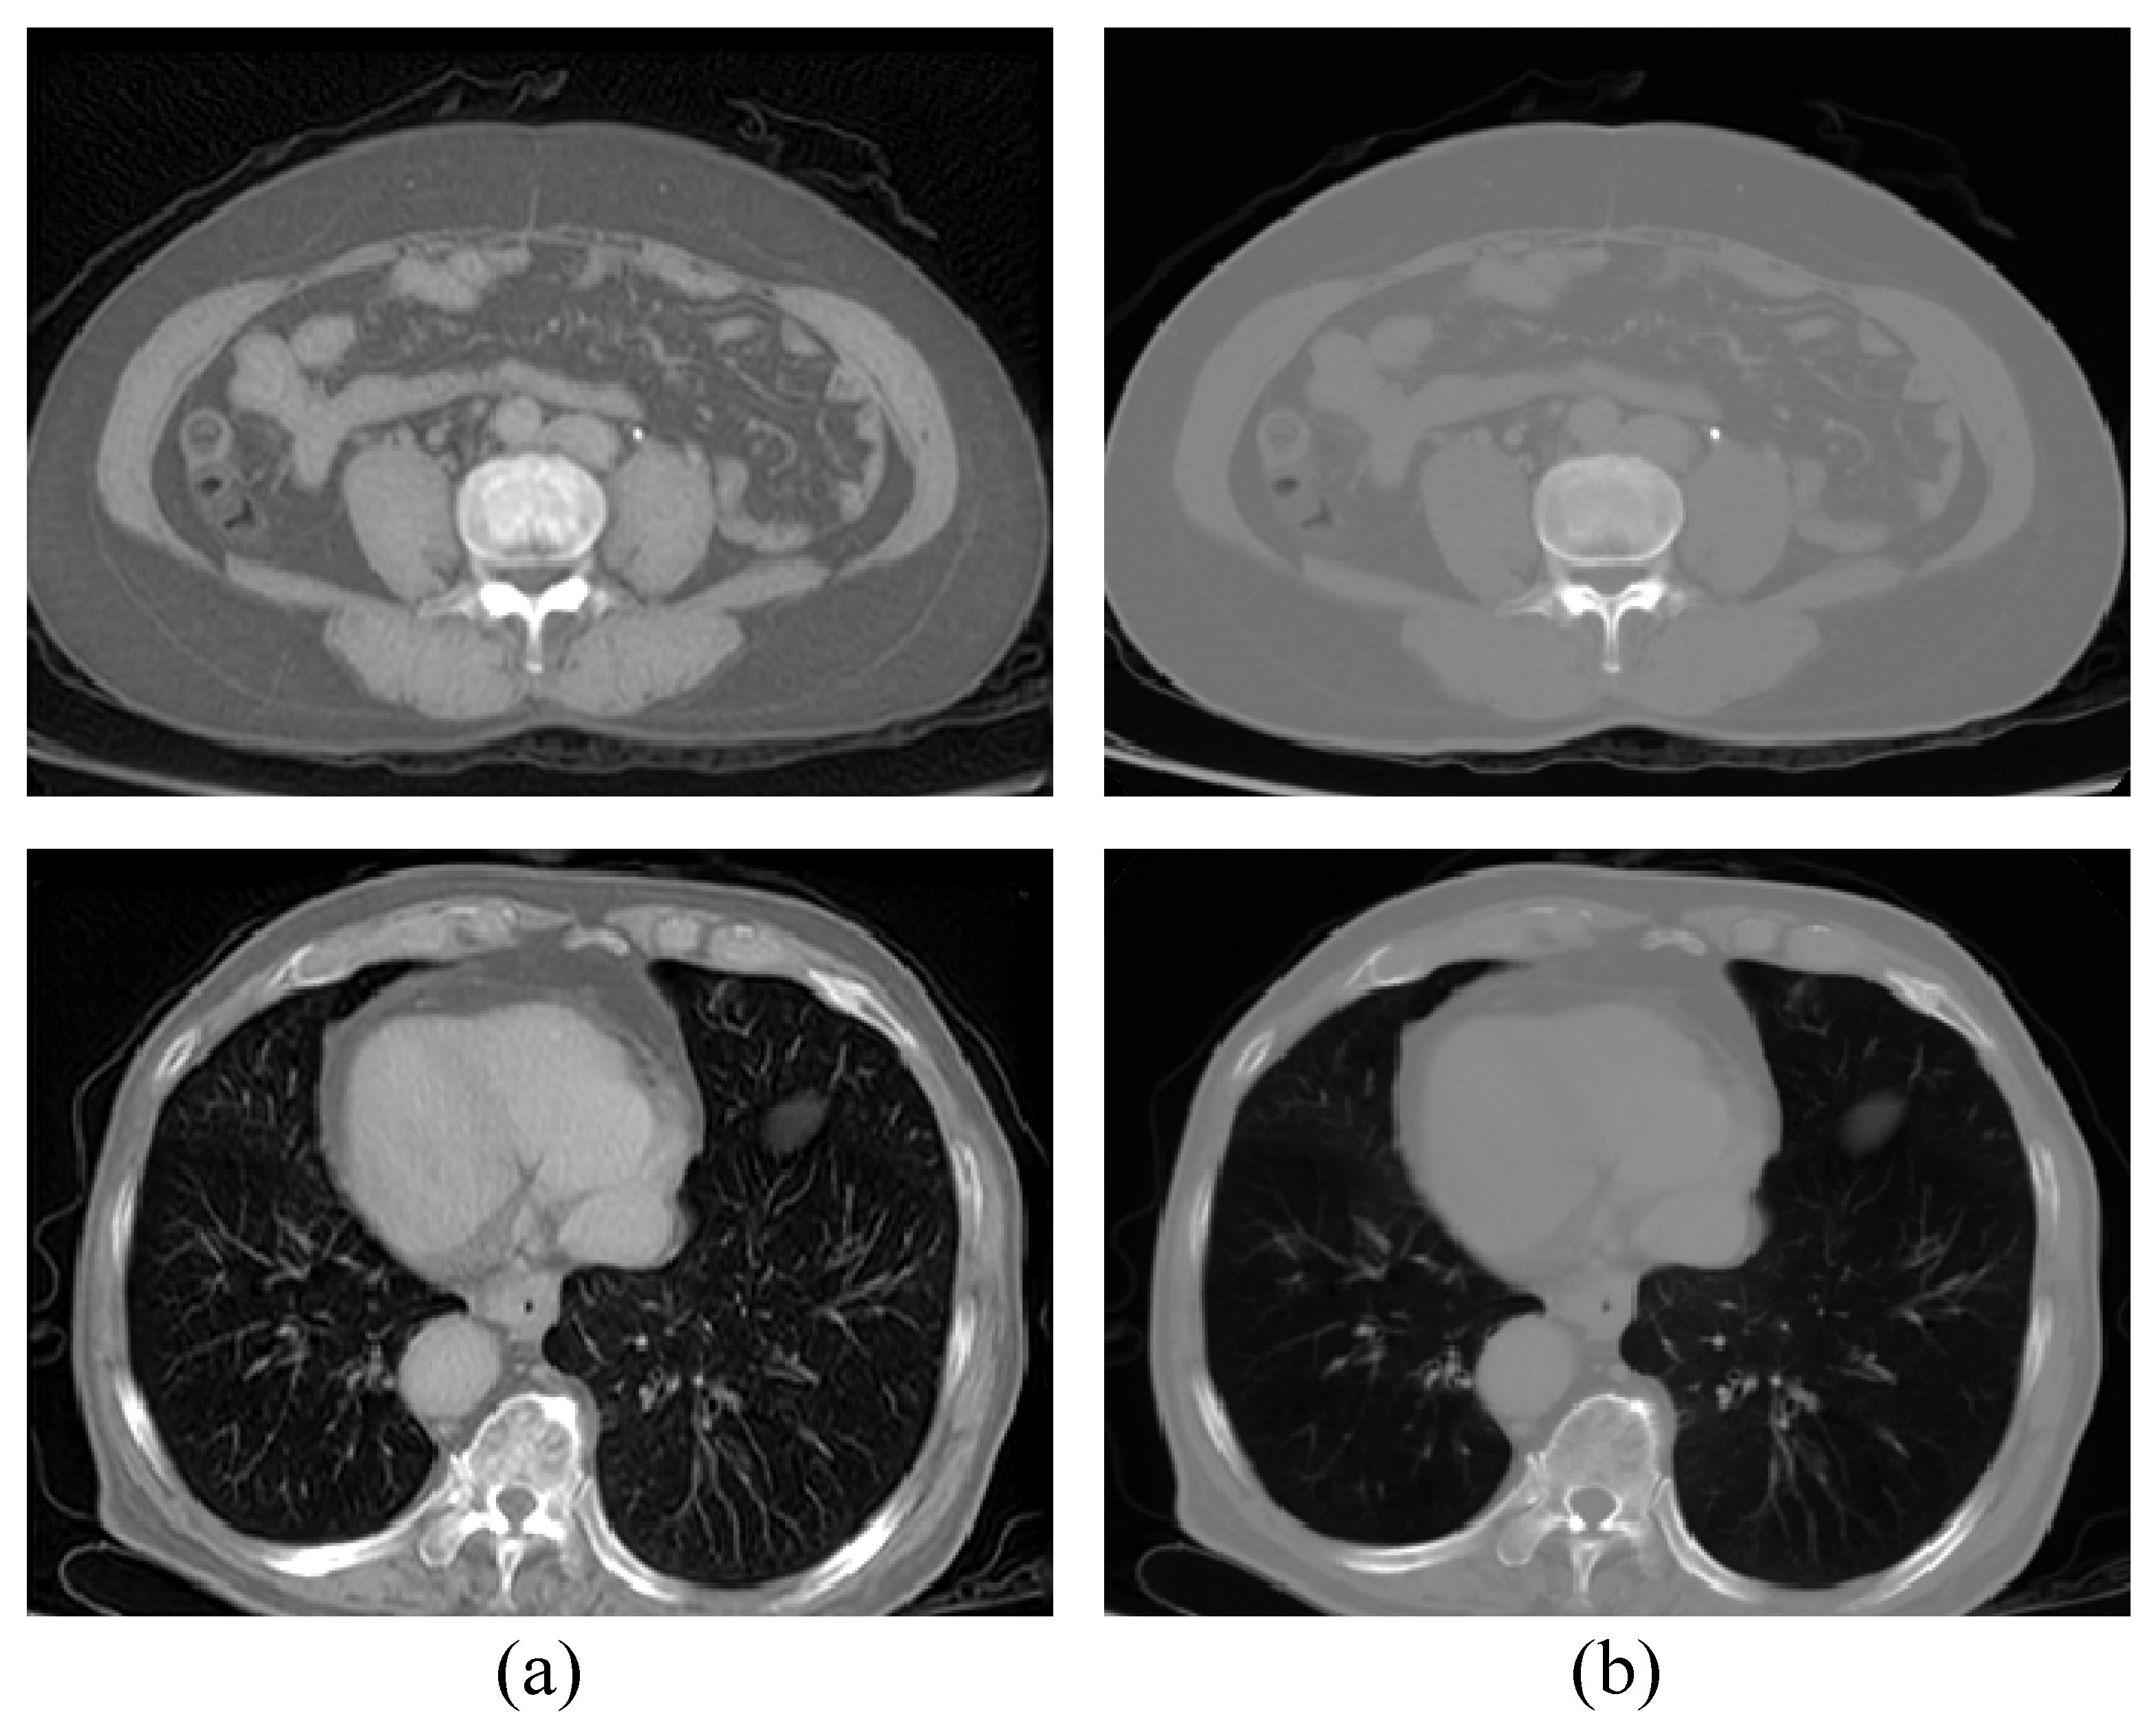

4.2. Quantitative and Qualitative Results